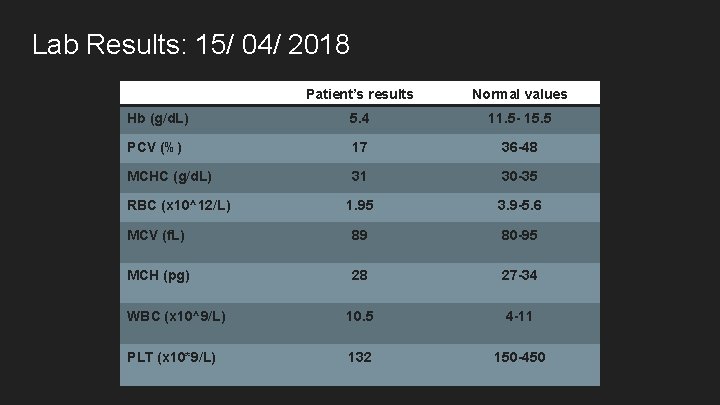

Lab Results: 15/ 04/ 2018 Patient’s results Normal values Hb (g/d. L) 5. 4 11. 5 - 15. 5 PCV (%) 17 36 -48 MCHC (g/d. L) 31 30 -35 1. 95 3. 9 -5. 6 MCV (f. L) 89 80 -95 MCH (pg) 28 27 -34 WBC (x 10^9/L) 10. 5 4 -11 PLT (x 10*9/L) 132 150 -450 RBC (x 10^12/L)